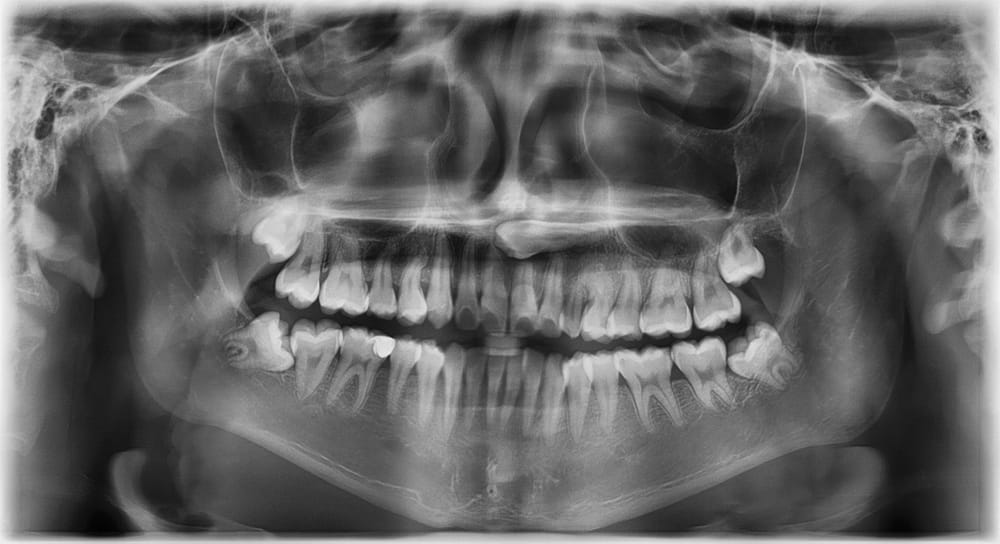

It’s important to make an appointment to see us at Jacaranda Dental as soon as possible if you are experiencing any wisdom teeth symptoms. Early intervention can prevent more severe complications, such as infections, damage to other teeth, or bone loss. We will examine your mouth and likely take X-rays to assess the position and condition of your wisdom teeth. If there is insufficient space for them to emerge correctly or they are impacted, we may recommend removal.

Not everyone will need their wisdom teeth removed. Regular dental check-ups and X-rays allow us to monitor their growth and catch any issues early. If your wisdom teeth emerge without causing problems, they may not require extraction.